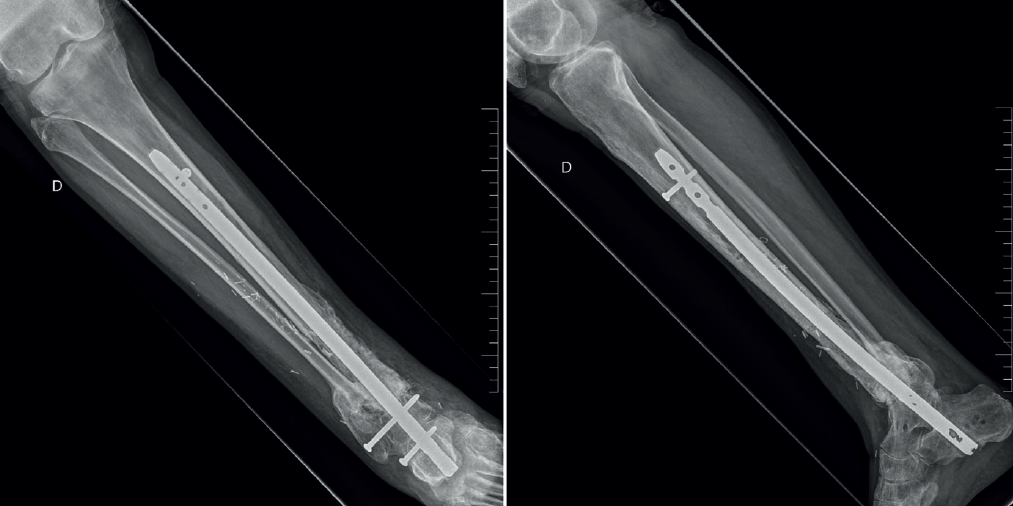

Figura 8. Control radiológico postoperatorio del segundo tiempo quirúrgico. Aporte de injerto óseo y artrodesis tibiotalocalcánea mediante clavo retrógrado.

Posteriormente, se estabiliza el miembro mediante un clavo retrógrado de artrodesis tibiotalocalcánea (Figura 8).

A los 6 meses tras la cirugía se observa consolidación completa del injerto en las radiografías, ausencia de síntomas de infección y normalización de la PCR y la VSG en las analíticas de control.

El paciente presenta una dismetría del miembro afectado de 25 mm (Figura 9) que se corrige con un alza.

Un año tras la cirugía, el paciente se encuentra bien, sin dolor en la pisada, no presenta signos ni síntomas de inflamación y las analíticas son normales (Figura 10). En las radiografías se observa consolidación completa (Figura 11).